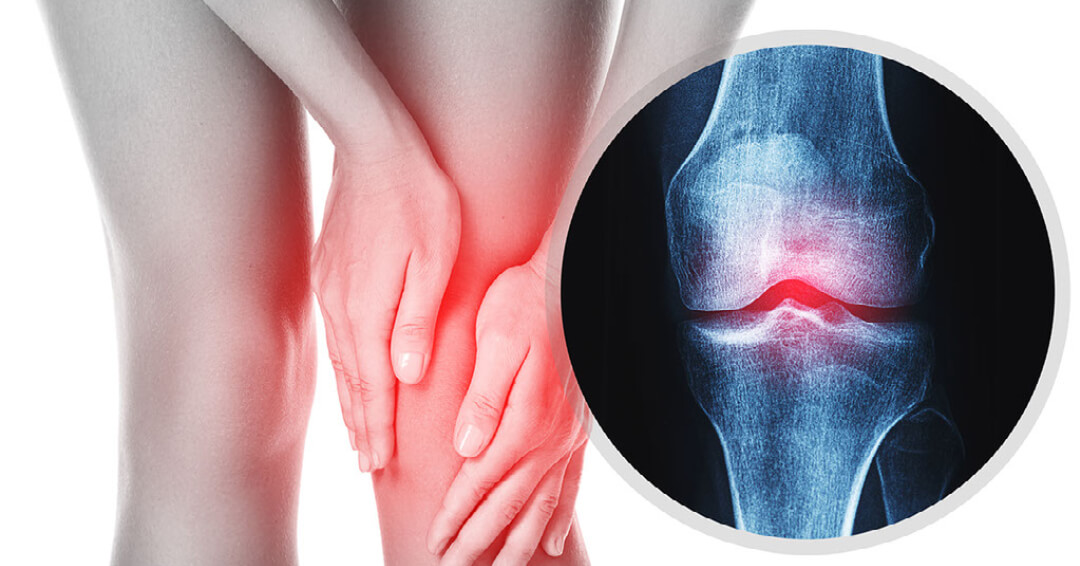

무릎관절염은 무릎에 염증이 생기고 관절이 손상돼 통증과 뻣뻣함이 나타나는 질환입니다. 무릎관절염은 크게 골관절염, 류마티스 관절염, 외상 후 관절염 등 3가지 유형이 있습니다.

골관절염은 무릎관절염의 가장 흔한 유형으로 관절을 완충하는 연골이 점진적으로 마모되면서 발생합니다. 이는 뼈가 서로 마찰되어 무릎 관절에 통증, 붓기, 뻣뻣함을 유발할 수 있습니다. 골관절염의 위험 요인으로는 나이, 비만, 유전, 관절 부상, 과용 등이 있습니다.

류마티스 관절염은 신체의 면역체계가 관절을 공격해 염증과 손상을 일으키는 자가면역질환입니다. 이는 무릎 관절에 통증, 붓기, 뻣뻣함, 변형을 초래할 수 있습니다. 류마티스 관절염의 위험요인으로는 유전, 흡연, 특정 바이러스나 박테리아에 대한 노출이 포함됩니다.

외상 후 관절염은 무릎 관절에 골절이나 인대 파열 등의 부상을 입은 후 발병하는 관절염의 일종입니다. 이는 무릎의 연골과 뼈에 손상을 일으켜 통증, 붓기, 뻣뻣함을 유발할 수 있습니다.

무릎 관절염 증상

무릎 관절염의 증상은 아래와 같지만, 이러한 증상이 초기에 발견되었을 때 미리 병원에 가서 검사를 받아보길 추천드립니다.

무릎 관절염의 대표적인 증상으로는 다음과 같습니다.

- 체중을 견디거나 신체활동을 하는 동안의 무릎 관절 통증

- 무릎 관절의 경직, 특히 아침이나 활동하지 않는 기간에서의 경직

- 무릎 관절의 붓기 또는 압통

- 무릎 관절에 금이 가거나 터지는 느낌

- 무릎 관절의 운동범위 감소

- 무릎 관절의 약화 또는 불안정

- 심한 경우 무릎 관절의 변형

이러한 증상이 발생할 경우 병원에 가서 검사를 받아보길 바라며, 무엇보다 근본 원인을 파악하고 적절한 치료 계획을 수립하는 것이 중요합니다. 무릎 관절염의 치료 종류에는 약물 치료, 물리치료, 보조 장치, 생활방식의 변화, 심각한 경우 수술 등이 있는데, 무엇보다도 평소에 무릎 관절을 무리시키지 않는 행동을 하는 것이 중요하다고 말씀드리겠습니다.